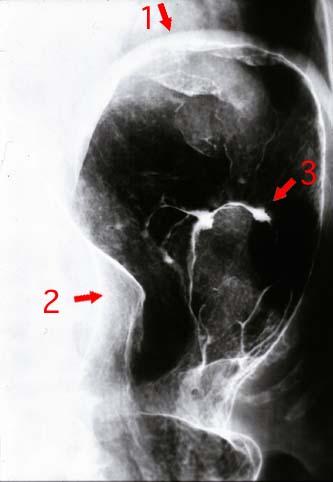

多発腫瘍を主体とした進行胃悪性リンパ腫のX線像  立位による胃の二重造影写真で、(id:2279)のBの写真を拡大したものです。胃の穹窿部の前壁にある病変(矢印1)、胃体上部小弯にある病変(矢印2)および胃体上部後壁にある病変(矢印3)が、それぞれ認められます。これら3個の腫瘤の間には、正常の粘膜が介在しています。